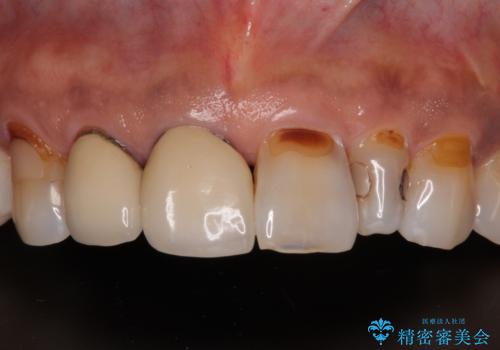

- 矮小歯である前歯がしみるとのことで来院された患者様です。

上顎前歯の歯肉ラインにエナメル質の欠損が認められ、そこが原因で冷たいものがしみている状態でした。

歯の大きさが小さいこと、隣の歯や反対側のセラミッククラウンの境目が見えていることなどから、前歯4本あるいは6本に対して、オールセラミッククラウンによる補綴治療をご提案しました。